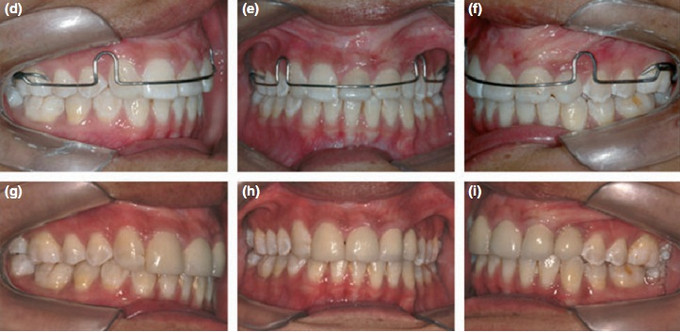

女,十岁,单侧唇腭裂致21牙、22、12牙畸形,且21牙、22牙间牙槽骨发育不全。经自体髂嵴骨移植后,拔除21牙、22牙行正畸治疗以将23牙移动至22牙位置。同时将正畸需拔除的下颌第一前磨牙移植到21牙的牙槽窝内。并在正畸治疗结束后树脂恢复21牙、22牙形态。患者18岁时拔除左上颌乳尖牙行种植义齿修复。